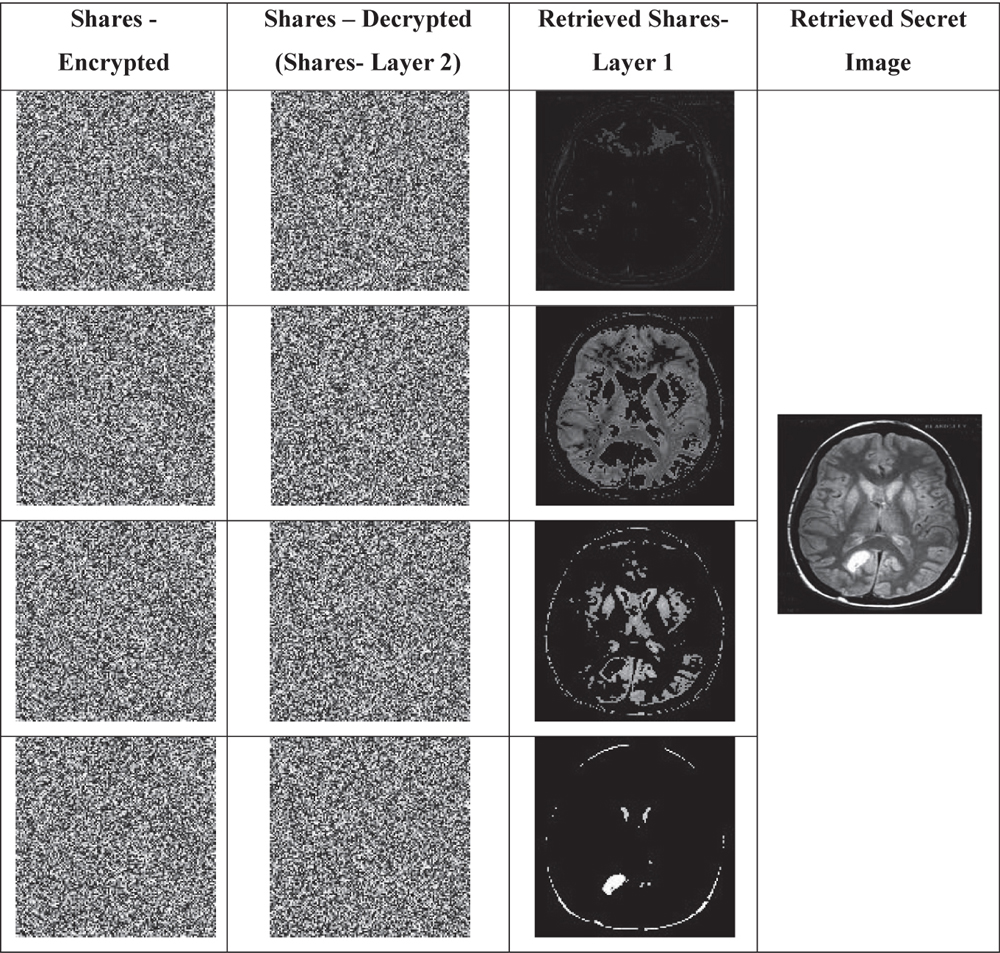

Table 3 Secret image reconstruction results

In above Table 3, the intermediate results obtained with the proposed Secret image Reconstruction method is provided. The Encrypted shares maintained by the trusted party are given in first column. Next column gives the decrypted shares (representing the shares produced at second layer), which is shared with the authenticated clients. Third column represents the retrieved shares from first layer and finally the reconstructed secret image is provided in fourth column.